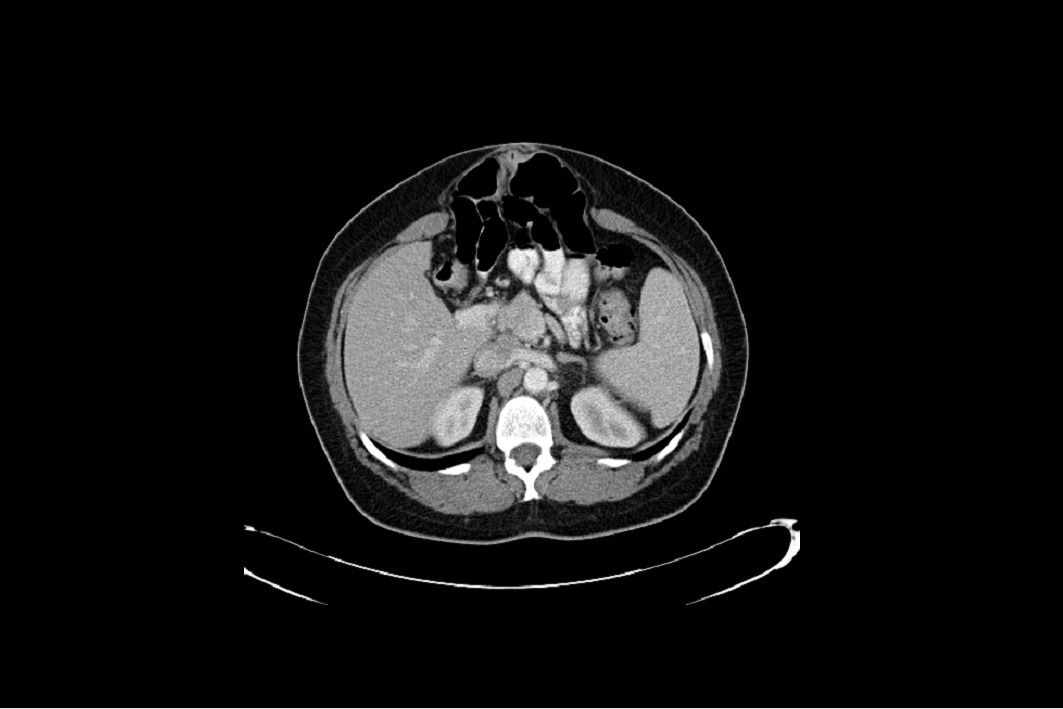

Back in January 2004 I was diagnosed with a large Hiatal Hernia with extreme GERD I then had a laparoscopic Nissen Fundoplication to try and repair this. After the surgery I still felt the sliding up and down motion and found it hard to breathe. I then went back to the surgeon that repaired it and he said it was fixed. I knew It wasn’t right, so I went and searched for other doctors. I found a doctor out of state and he also said I did not have a Hiatal Hernia. I told him I had “A knocking below my sternum” and so he removed half of it this left a Ventral and Incisional Hernia and I still felt an up and down motion leaving me extremely short of breath. I then found another G.I. doctor who found the problem. I had a large Sliding Hiatal Hernia at the 35cm at the E.G. Junction with the Nissen intact. He referred me to a surgeon who confirmed a Ventra Hernia with many adhesions. He never repaired the Hiatal Hernia, but the mesh and adhesion removal helped, and I’ve been functional for 14 years. However, I started working at a wholesale club where I had to twist and bend while lifting heavy things. At the same time, I contracted Bronchitis and I coughed a lot and gagged. I felt something pop and then all my symptoms began. I was able to get a surgeon right a way who did a CAT Scan. The CAT Scan showed a large Ventral and Abdominal Wall Hernia. My stomach, liver, and intestines were protruding outside my Ventral and abdominal wall. The next day they performed emergency surgery. I had my original paperwork from 2004 but they refused to see it. They opened me up and put mesh in the Ventral and Abdominal Wall. This seem to only make my breathing and sliding of my Hiatal Hernia worse. They said I did not have/ did not see a Hiatal Hernia. This seems impossible because they don’t just magically disappear. A week and a half post-surgery every time I breathe or talk it feels like my stomach is moving up and down and slamming into the mesh they placed in the Ventral area. I am unable to eat, sleep, or breath very well. I do not have any quality of life because I am too out of breath and this big bulge comes up when I breathe. I have told them of my symptoms, but the surgeon says he will not do anything until the surgery heals. I feel helpless and feel with every breathe I am going to die. I can’t eat so I am very weak. I need help fast and I don’t know what to do.

Back in January 2004 I was diagnosed with a large Hiatal Hernia with extreme GERD I then had a laparoscopic Nissen Fundoplication to try and repair this. After the surgery I still felt the sliding up and down motion and found it hard to breathe. I then went back to the surgeon that repaired it and he said it was fixed. I knew It wasn’t right, so I went and searched for other doctors. I found a doctor out of state and he also said I did not have a Hiatal Hernia. I told him I had “A knocking below my sternum” and so he removed half of it this left a Ventral and Incisional Hernia and I still felt an up and down motion leaving me extremely short of breath. I then found another G.I. doctor who found the problem. I had a large Sliding Hiatal Hernia at the 35cm at the E.G. Junction with the Nissen intact. He referred me to a surgeon who confirmed a Ventra Hernia with many adhesions. He never repaired the Hiatal Hernia, but the mesh and adhesion removal helped, and I’ve been functional for 14 years. However, I started working at a wholesale club where I had to twist and bend while lifting heavy things. At the same time, I contracted Bronchitis and I coughed a lot and gagged. I felt something pop and then all my symptoms began. I was able to get a surgeon right a way who did a CAT Scan. The CAT Scan showed a large Ventral and Abdominal Wall Hernia. My stomach, liver, and intestines were protruding outside my Ventral and abdominal wall. The next day they performed emergency surgery. I had my original paperwork from 2004 but they refused to see it. They opened me up and put mesh in the Ventral and Abdominal Wall. This seem to only make my breathing and sliding of my Hiatal Hernia worse. They said I did not have/ did not see a Hiatal Hernia. This seems impossible because they don’t just magically disappear. A week and a half post-surgery every time I breathe or talk it feels like my stomach is moving up and down and slamming into the mesh they placed in the Ventral area. I am unable to eat, sleep, or breath very well. I do not have any quality of life because I am too out of breath and this big bulge comes up when I breathe. I have told them of my symptoms, but the surgeon says he will not do anything until the surgery heals. I feel helpless and feel with every breathe I am going to die. I can’t eat so I am very weak. I need help fast and I don’t know what to do.